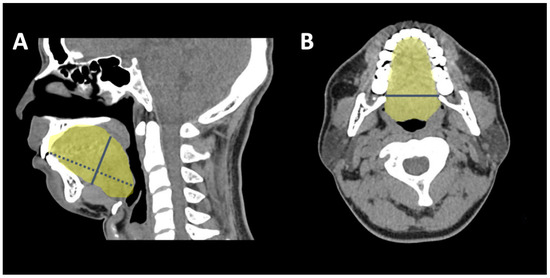

2.4. 3-D CT Measuring Algorithm